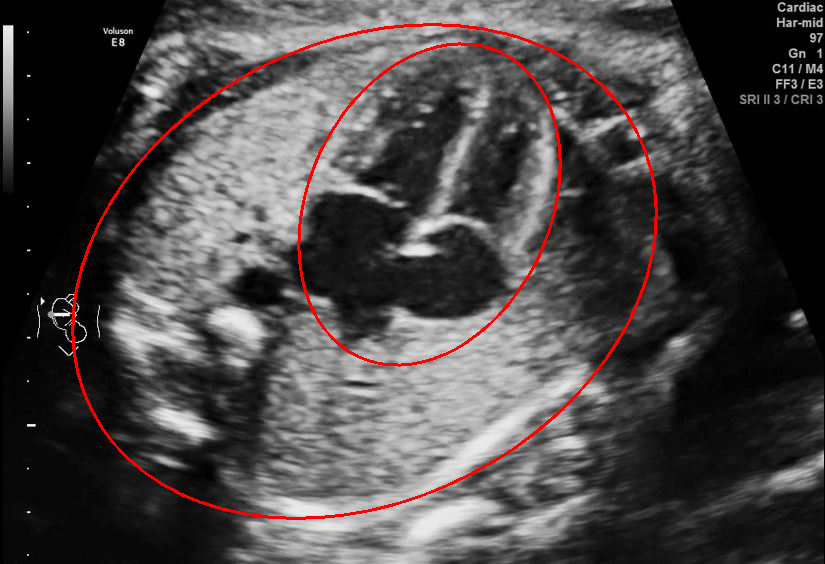

Visualization results of different methods.

Although the segmentation model trained on the fetal ultrasound dataset achieves a relative high average dice scores averaging over 0.9, the fitted ellipse highly depends on the segmentation results. As shown in the middle row of Fig. 2, the segment-based ellipse-fit method performs well when the image quality is good (first row), but the performance degrades when the segmentation is affected by image artifacts such as the acoustic shadowing (second and third row). Our proposed method is more robust to image quality and shadows. We also tried to compare to the GPN [9] with their open source code on our dataset, however, the results are not comparable to ours and those presented in Table. 1. It is difficult to conclude whether it is caused by the network itself or the training strategies. We, therefore, did not include the comparative results in this work.

As shown in Fig. 3 , both the proposed ellipse regression loss and IoU loss are necessary for ellipse detection. If the EllipseNet only supervised by IoU loss (first column), the model fails to optimize the major and minor axis separately, and the predicted ellipses degenerate into circles like the CircleNet. It is clear that the supervision of IoU loss can help to improve the prediction of location and shape (first and second row) and to correct the angle (last row).